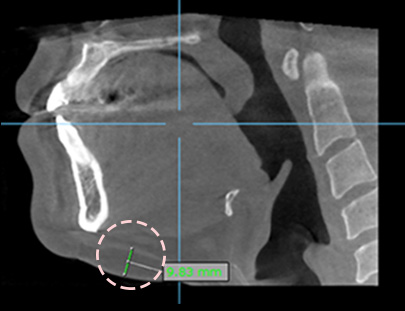

After 3D-CT scanning,

a consultation is carried out to

more precisely identify

the fat areas

· A very fine 0.9mm tip targets and removes only facial fat

ATOP Plastic Surgery's facial liposuction is not a liposuction that is simply removed according to the feeling of the touch, but a surgical procedure that checks the 3D CT roll and removes the inner branches of the muscles. ATOP has a variety of know-how in facial liposuction, and with its high technology, it removes fat in the muscle layer to make the suction effect more pronounced and last for a long time.